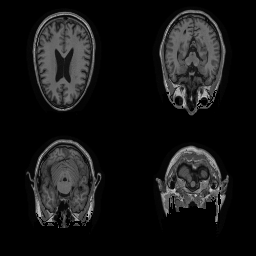

| Original | Renderings after de-identification | Original | MRI slices after de-identification | ||||||

| CP-GAN | FACE MASK | DEFACE | QUICKSHEAR | CP-GAN | FACE MASK | DEFACE | QUICKSHEAR | ||

Benchmark De-Identification Methods. We compare our result with three publicly available and widely-established methods for de-identification of MRI head scans, depicted in Figure 3. All methods have in common that they (1) are not deep-learning-driven, (2) require no additional training and (3), are used on a day-to-day basis in neuroscience and clinical research. All procedures were applied with default settings on images of resolution . The methods include QUICKSHEAR [Schimke et al.(2011)Schimke, Kuehler, and Hale], FACE MASK [Milchenko and Marcus(2013)], and DEFACE [Bischoff-Grethe et al.(2007)Bischoff-Grethe, Ozyurt, Busa, Quinn, Fennema-Notestine, Clark, Morris, Bondi, Jernigan, Dale, Brown, and Fischl]. Descriptions of the methods are provided in the Appendix. We also include MRI WATERSHED [Ségonne et al.(2004)Ségonne, Dale, Busa, Glessner, Salat, Hahn, and Fischl], a skull-stripping method that removes everything except the brain.